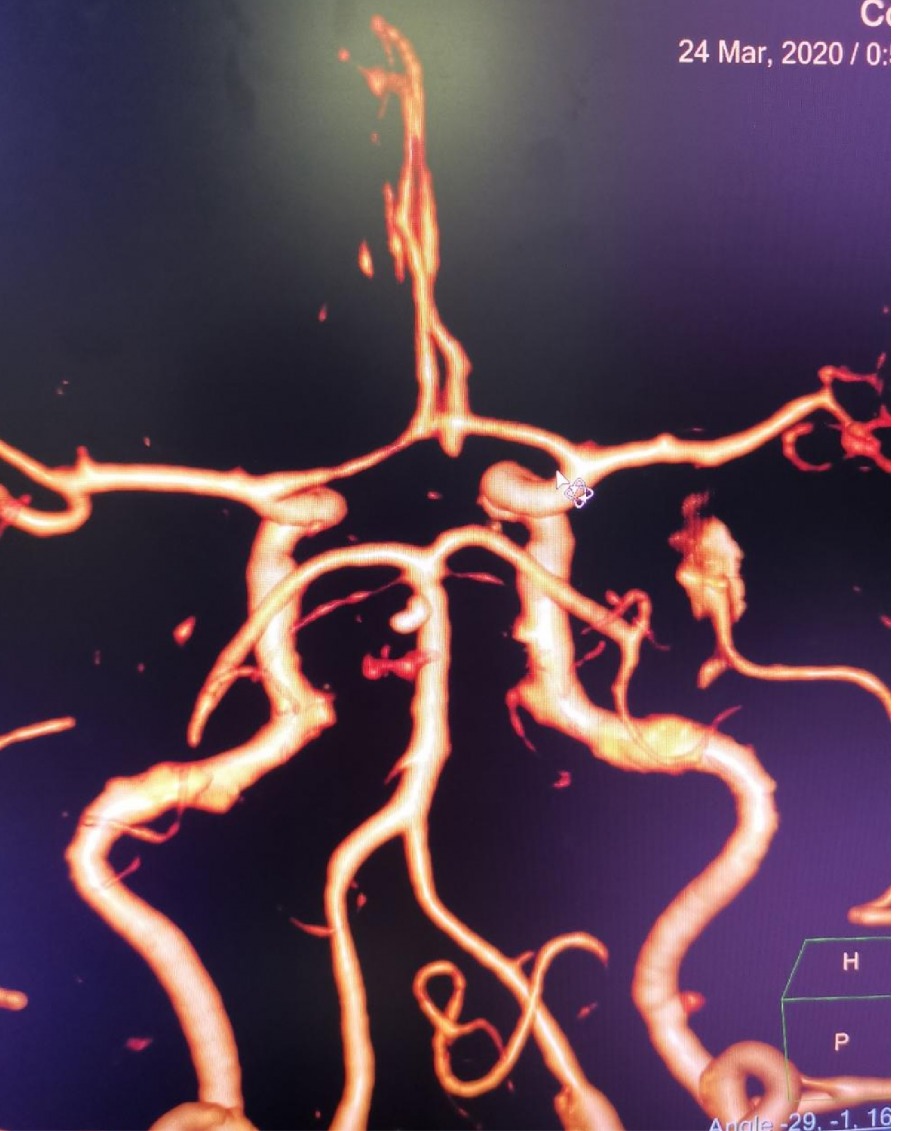

CTA 结果

本次⼊院⾏DSA检查:PICA供⾎区有畸形⾎管团,引流到横窦

术后CTA显⽰

术后CTA显⽰:畸形⾎管团消失